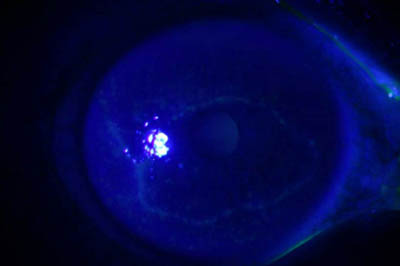

Tinción CW

Blanco de Calcofluor + Azul de Evans

Magnificación 160x